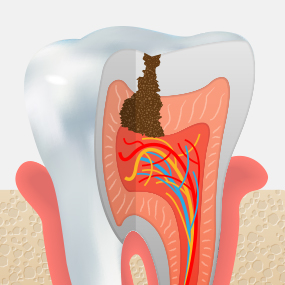

충치가 어느 정도 진행되었는지에 따라 치료 방법은 크게 달라질 수 있습니다. 서울하나치과는 정밀 진단을 통해 치아를 최대한 보존할 수 있는 치료법을 안내해드립니다.

CARIES TREATMENT

법랑질 안쪽에 있는 상아질까지 충치가 진행되어 뜨겁거나 차가운 음식을 먹으면 시린 증상이 나타납니다.